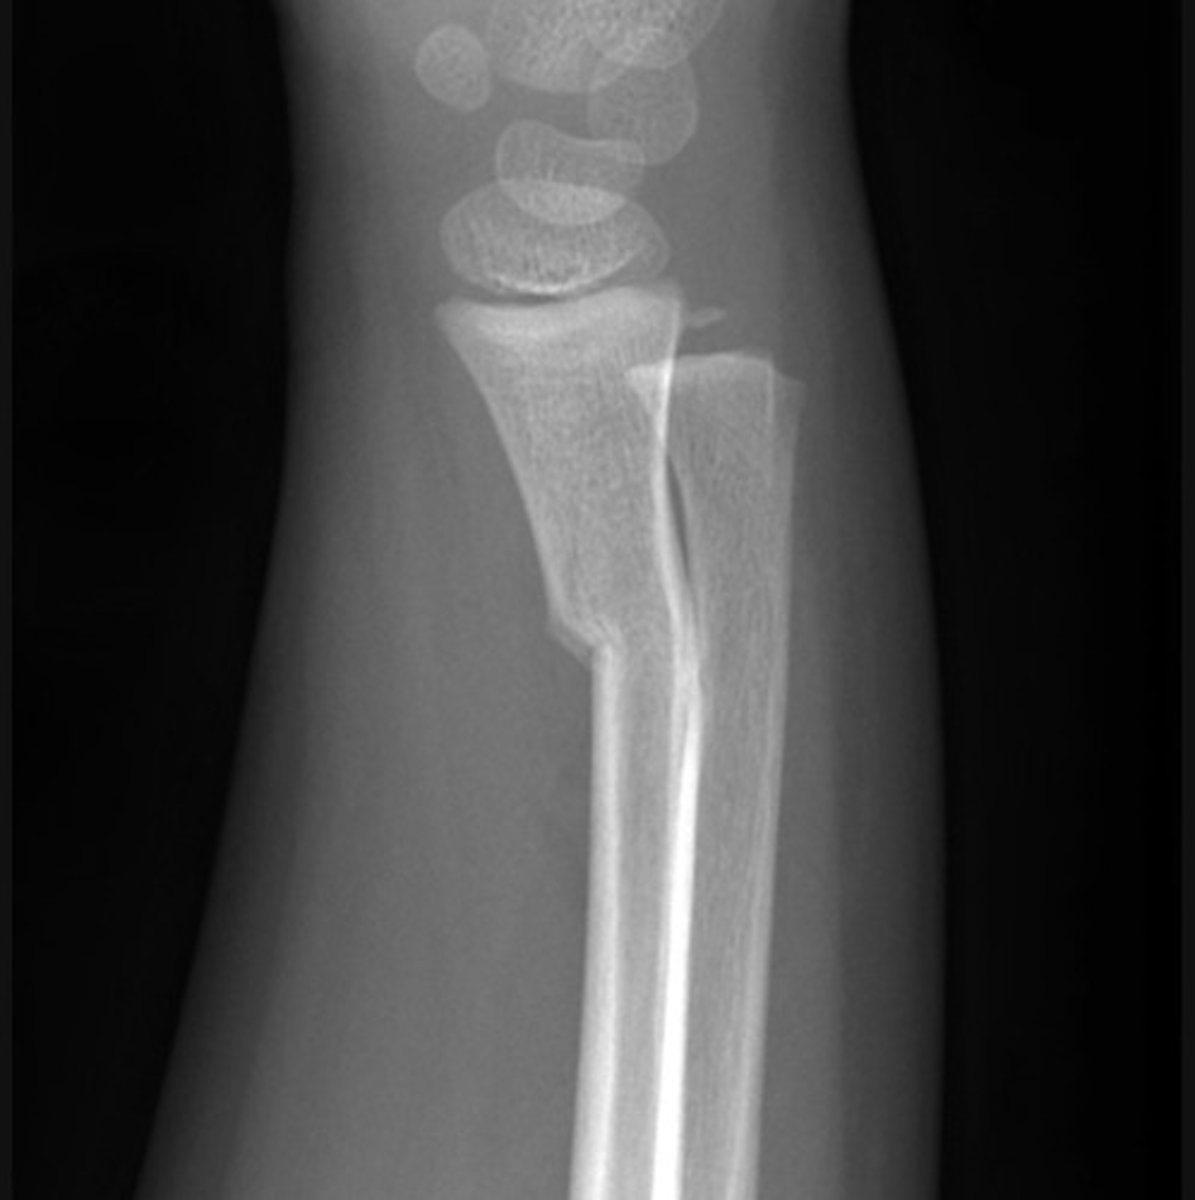

Monteggia fracture-dislocation - Lateral

a fracture of the ulnar shaft with dislocation of the radial head at the elbow

The radiocapitellar line should pass through the middle of the capitulum of the humerus